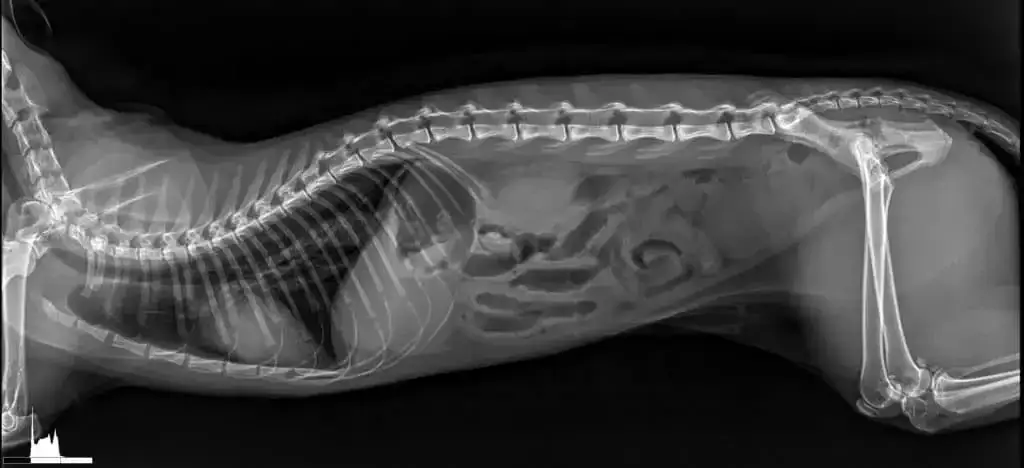

Przeswietlenie u weterynarza, znane również jako RTG, jest kluczowym badaniem diagnostycznym dla naszych pupili. Koszt przeswietlenia dla psów i kotów w Polsce waha się od 70 do 90 zł, ale ceny mogą znacznie różnić się w zależności od lokalizacji kliniki. W większych miastach, takich jak Warszawa, Kraków czy Wrocław, ceny mogą osiągać nawet 254,12 zł, co sprawia, że warto porównać oferty różnych klinik.

Średnia cena badania rentgenowskiego dla psa lub kota wynosi około 223,30 zł. W mniejszych miejscowościach i wsiach ceny są zazwyczaj niższe i wahają się od 197,65 zł do 210 zł. Dodatkowo, koszt przeswietlenia łapy psa może wynosić od 100 do 300 zł, a w przypadku kilku podstawowych projekcji RTG cena może sięgać 200 do 350 zł.

W miarę jak technologia weterynaryjna się rozwija, przeswietlenie zwierząt staje się coraz bardziej dostępne i efektywne. Nowoczesne urządzenia RTG, takie jak aparaty cyfrowe, oferują znacznie wyższą jakość obrazów, co pozwala na dokładniejszą diagnostykę. Dzięki temu weterynarze mogą szybciej i skuteczniej identyfikować problemy zdrowotne, co może prowadzić do wcześniejszego rozpoczęcia leczenia i lepszych wyników dla zwierząt. Warto również zwrócić uwagę na innowacje w zakresie telemedycyny, które umożliwiają właścicielom zwierząt konsultacje z weterynarzami zdalnie, co może być szczególnie przydatne w przypadku pilnych sytuacji.